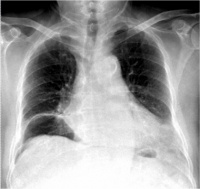

②B型超声检查:

Bk8b4.jpg

脾被摸下破裂

脾真性破裂

B超(左起图1脾中央破裂图2脾被摸下破裂图3脾真性破裂右图胃肠破裂穿孔)检查具有经济方便、可在床边检查、可重复进行动态观察、无创无痛、以及诊断准确率高等优点,因此其在腹部损伤的诊断中倍受重视.应用越来越广泛。 对肝、脾、肾等实质性脏器损伤,B超检查的确诊率达90%左右。可发现直径1— 2cm的实质

血肿,并可发现脏器包膜连续性中断和实质破裂等情况。超声检查对腹腔积液发现率很高。并可根据B超检查估计出腹腔积液的量,即每lcm液平段,腹腔积液约有500ml。由于气体对超声的反射强烈,其在声像图上表现为亮区。因此,B超检查也可发现腹腔内的积气,有助于空腔脏器破裂或穿孔的诊断。

急性胃穿孔。左叶肝前方见气体强回声